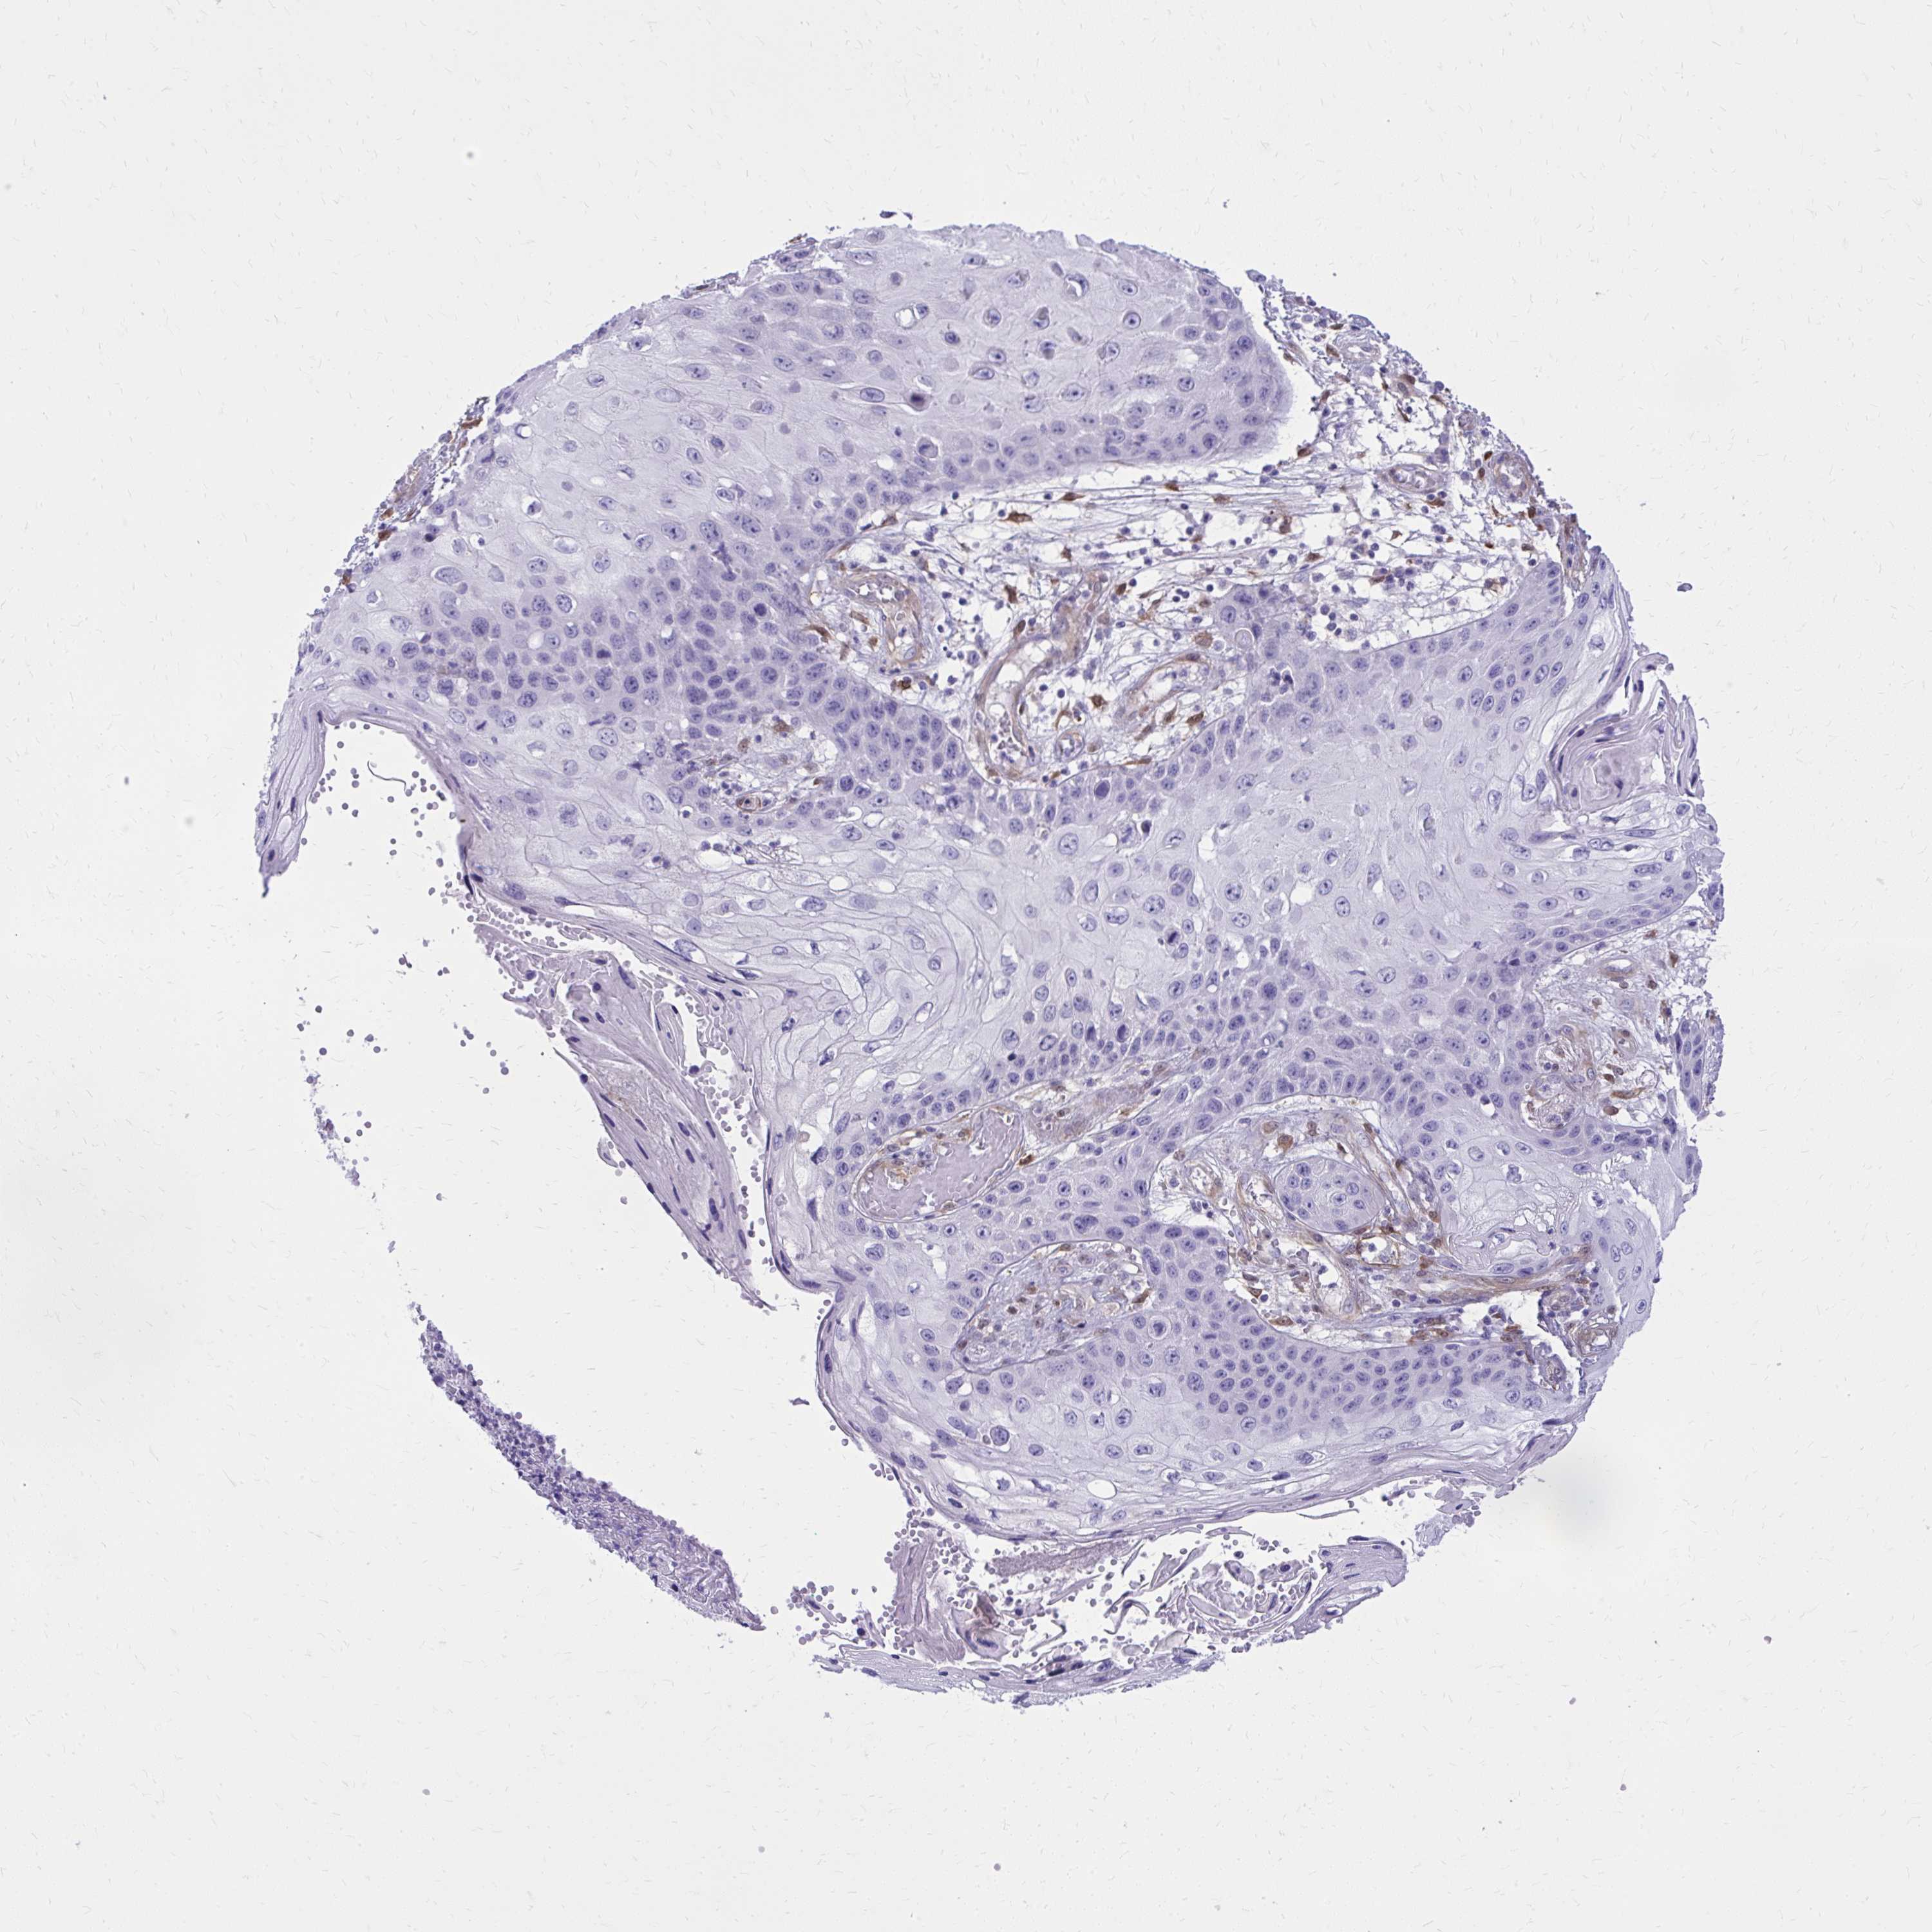

CANCER SKIN CANCER Show tissue menu

Basal cell and squamous cell cancer

SKIN CANCER - Protein expressioni

A mouse-over function shows sample information and annotation data. Click on an image to view it in a full screen mode. Samples can be filtered based on level of antibody staining by selecting one or several of the following categories: high, medium, low and not detected. The assay and annotation is described here.

Each image is clickable and will lead to virtual microscopy that enables deeper exploration of all samples and also displays staining intensity scores, fraction scores and subcellular localization as well as patient and tissue information for each sample.

Antibody HPA059180

Staining

High

Medium

Low

Not detected

Intensity

Strong

Moderate

Weak

Negative

Quantity

>75%

75%-25%

<25%

None

Location

Nuclear

Cytoplasmic/membranous

Cytoplasmic/membranous,nuclear

Basal cell carcinoma

Squamous cell carcinoma, NOS